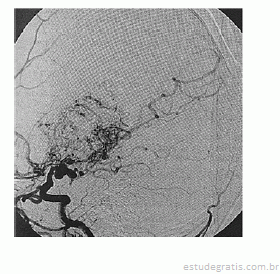

Paciente de 16 anos de idade, do sexo feminino, de asscendência japonesa, com deficits neurológicos progressivos iniciados ainda na infância, tem diagnóstico prévio de anemia falciforme. Realizou exame complementar de imagem do encéfalo, apresentado na reprodução acima. Há suspeita de doença de Moyamoya.